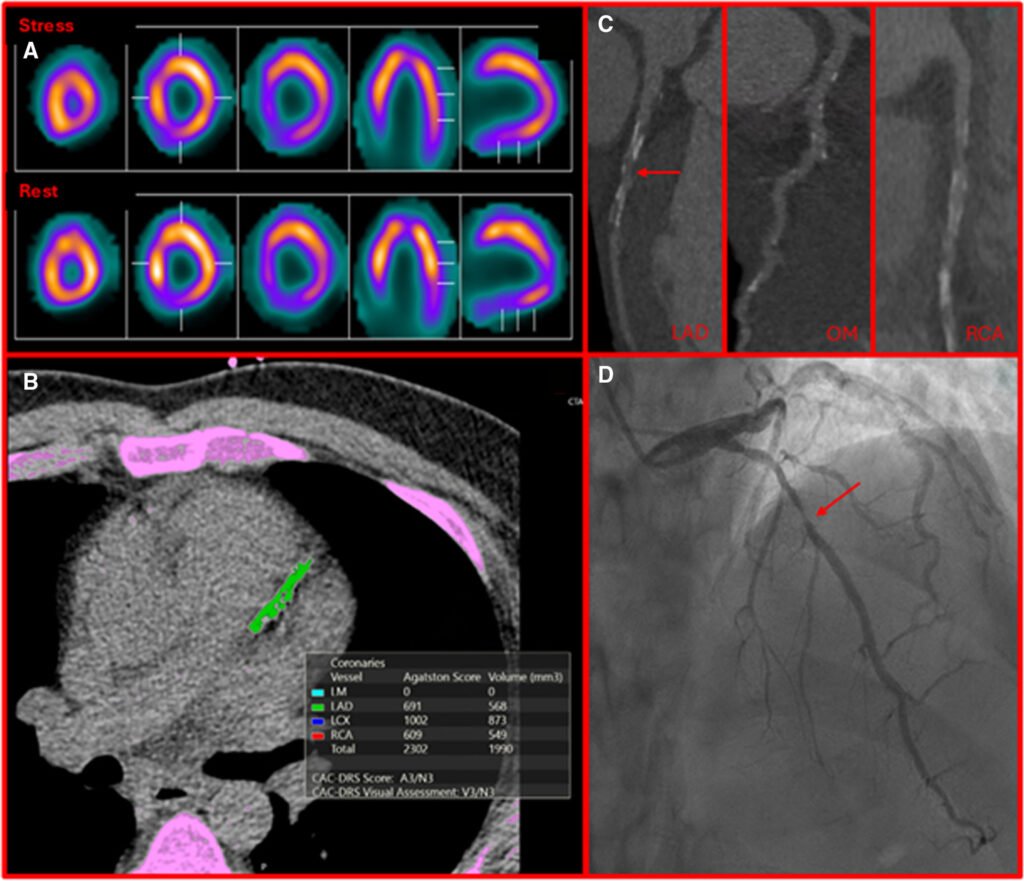

Onkološki pacijenti često nose značajan kardiovaskularni rizik već pre početka terapije. Najnoviji naučni stavovi ukazuju na fascinantno preklapanje ova dva sveta. Nije tajna da pušenje, dijabetes i hipertenzija „hrane” obe bolesti. Međutim, veza je mnogo dublja od samog stila života. Stvari postaju još ozbiljnije kada se uključi onkološka terapija. Zračenje, antraciklini i moderni inhibitori imunskih kontrolnih tačaka (ICI) direktni su učesnici u progresiji ateroskleroze.